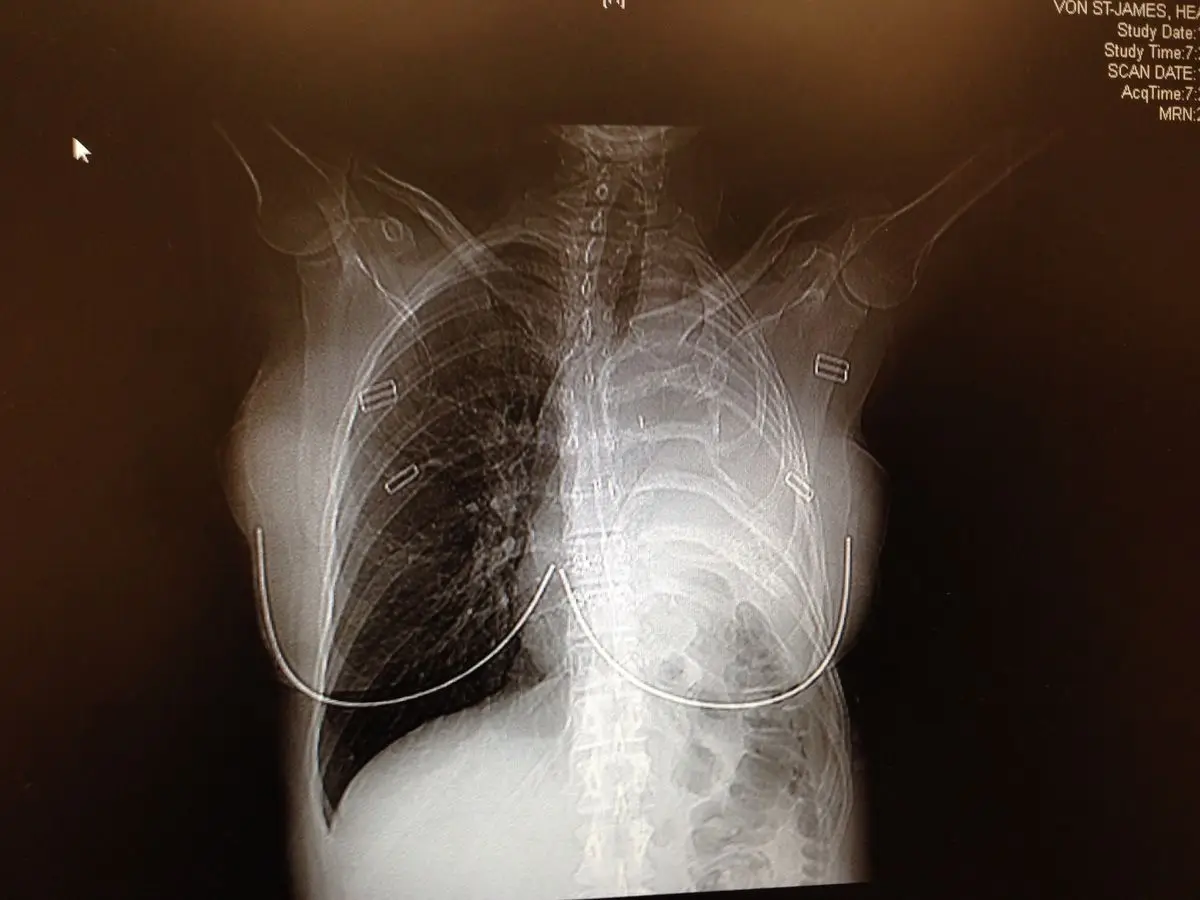

After giving birth by Caesarean section, the hairdresser went to see a doctor who put her through a CT scan, revealing a tumour near her lung.

Within two weeks, doctors diagnosed her with pleural mesothelioma, a rare and aggressive cancer linked to asbestos exposure. She was given around 15 months to live.

She underwent a complex operation in 2006 that involved removing her left lung, a rib, the pleura (the lining around the lung), part of her diaphragm, and the lining of her heart.